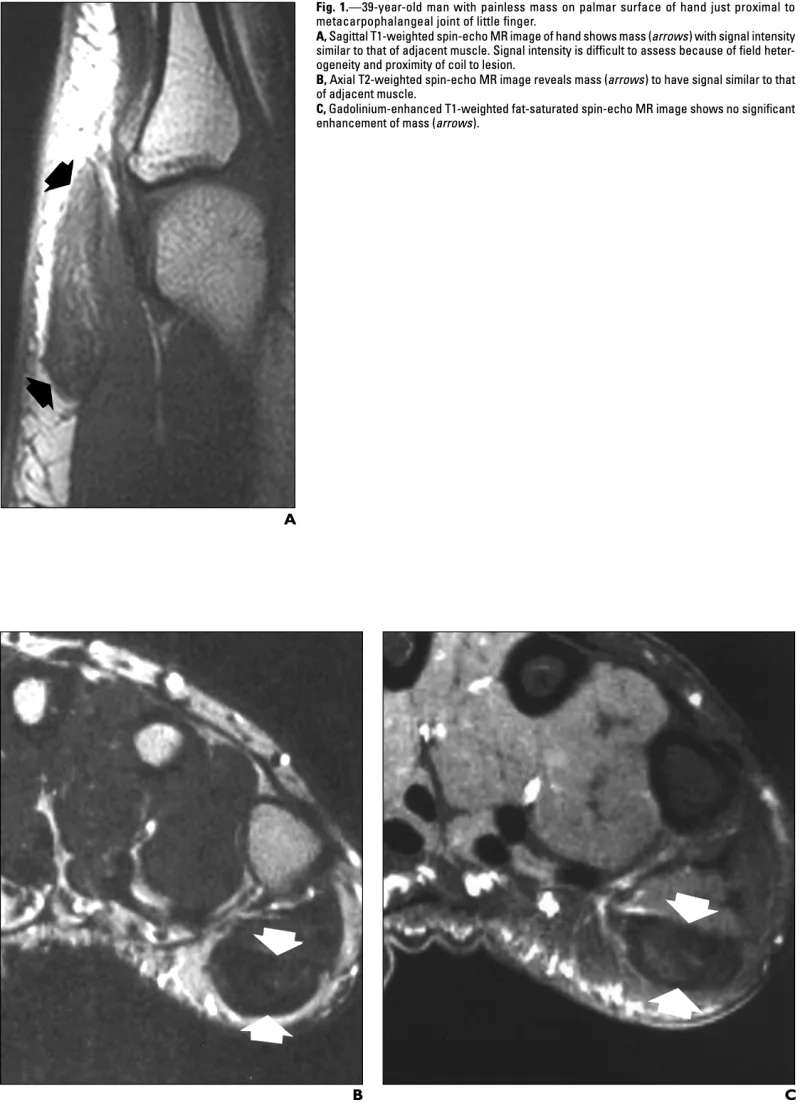

手指に生じた軟部腫瘍の摘出術で, 後輩医師が執刀.

T1強調画像(A), T2強調画像(B)で, 黒く描出され, 造影MRI(C)では, 淡く造影されて白く写ります.

以上のMRIの特徴は, 腱滑膜巨細胞腫と似ています.

引用元:Fox MG. MR imaging of fibroma of the tendon sheath. AJR Am J Roentgenol. 2003. 180.

術前MRIからは腱滑膜巨細胞腫を疑っていましたが, 開けてみると, 光沢のある白色で腱様の外観.

腱鞘線維腫が疑われる所見でした.